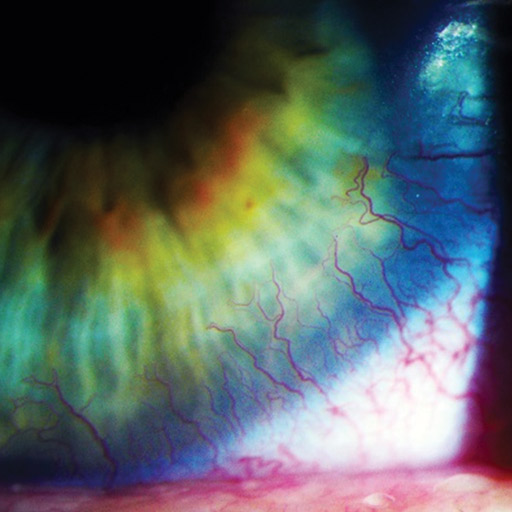

Corneal Neovascularization can be defined as the excessive growth of blood vessels that occurs at the level of the cornea. The main cause of the problem is represented by the oxygen deprivation. In healthy individuals, the cornea is transparent and it lacks vascularization. Both ocular insults and ocular hypoxia are responsible for the appearance of corneal vascularization.

- Limbal hyperemia (Redness around the cornea) – earliest sign of corneal neovascularization.

- Superficial vessels identified at the level of the cornea (single or multiple).

- In the situation that the deep stromal vessels are responsible for the corneal neovascularization, these are identified at the level of the cornea (sometimes accompanied by nerve fibres).

- Active engorged vessels and lipid exudate.

The invasion of the cornea by the deep stromal vessels presents the biggest risks, with the optical transparency being lost due to a series of changes. Among the most important changes, there are the hemorrhage and scarring that can occur at the level of the cornea. The deposits of lipids can also affect the optical transparency, complicating the already existent corneal neovascularization.